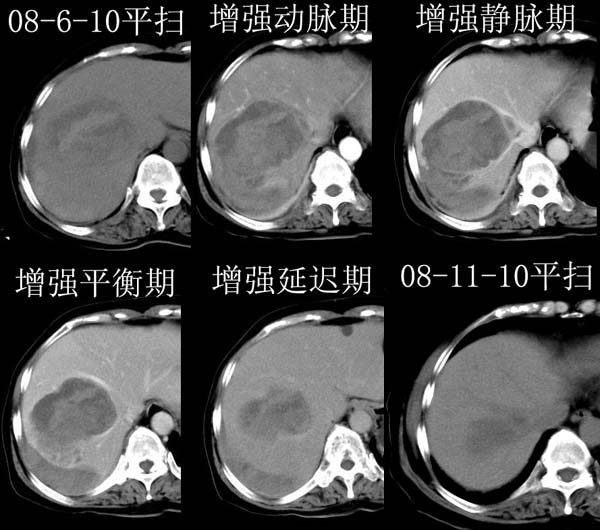

2008-6-10ct平扫

ct增强

2008-11-10ct平扫(其间去中山医院诊治未行特殊治疗)

2008-11-10ct平扫见并肝内、血膜下血肿基本吸收,肝内低密度灶缩小。此时再做增强ct应有显着意义。对患者/医者都好!

从平扫+增强及治疗后复查片,病变明显缩小,不考虑肝癌出血可能,还是考虑为良性病变可能性大;单纯血肿并包膜下积液吧,病变强化没法解释,肝血管破裂出血吧,增强不符合典型血管瘤的表现,良性肿瘤破裂出血吧,复查片看来好像也不太支持(没做强化也不太好说)。本人还是考虑单纯肝内血肿并包膜下积液,强化是不是血管有外渗。

患者自6月至11月,如果是肝癌,没有经过特殊治疗,想必应该会有所进展吧,而不是ct所见,反而似有病灶减小的趋势。建议增强。